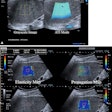

GE HealthCare features new ultrasound, MRI offerings at ECR 2024